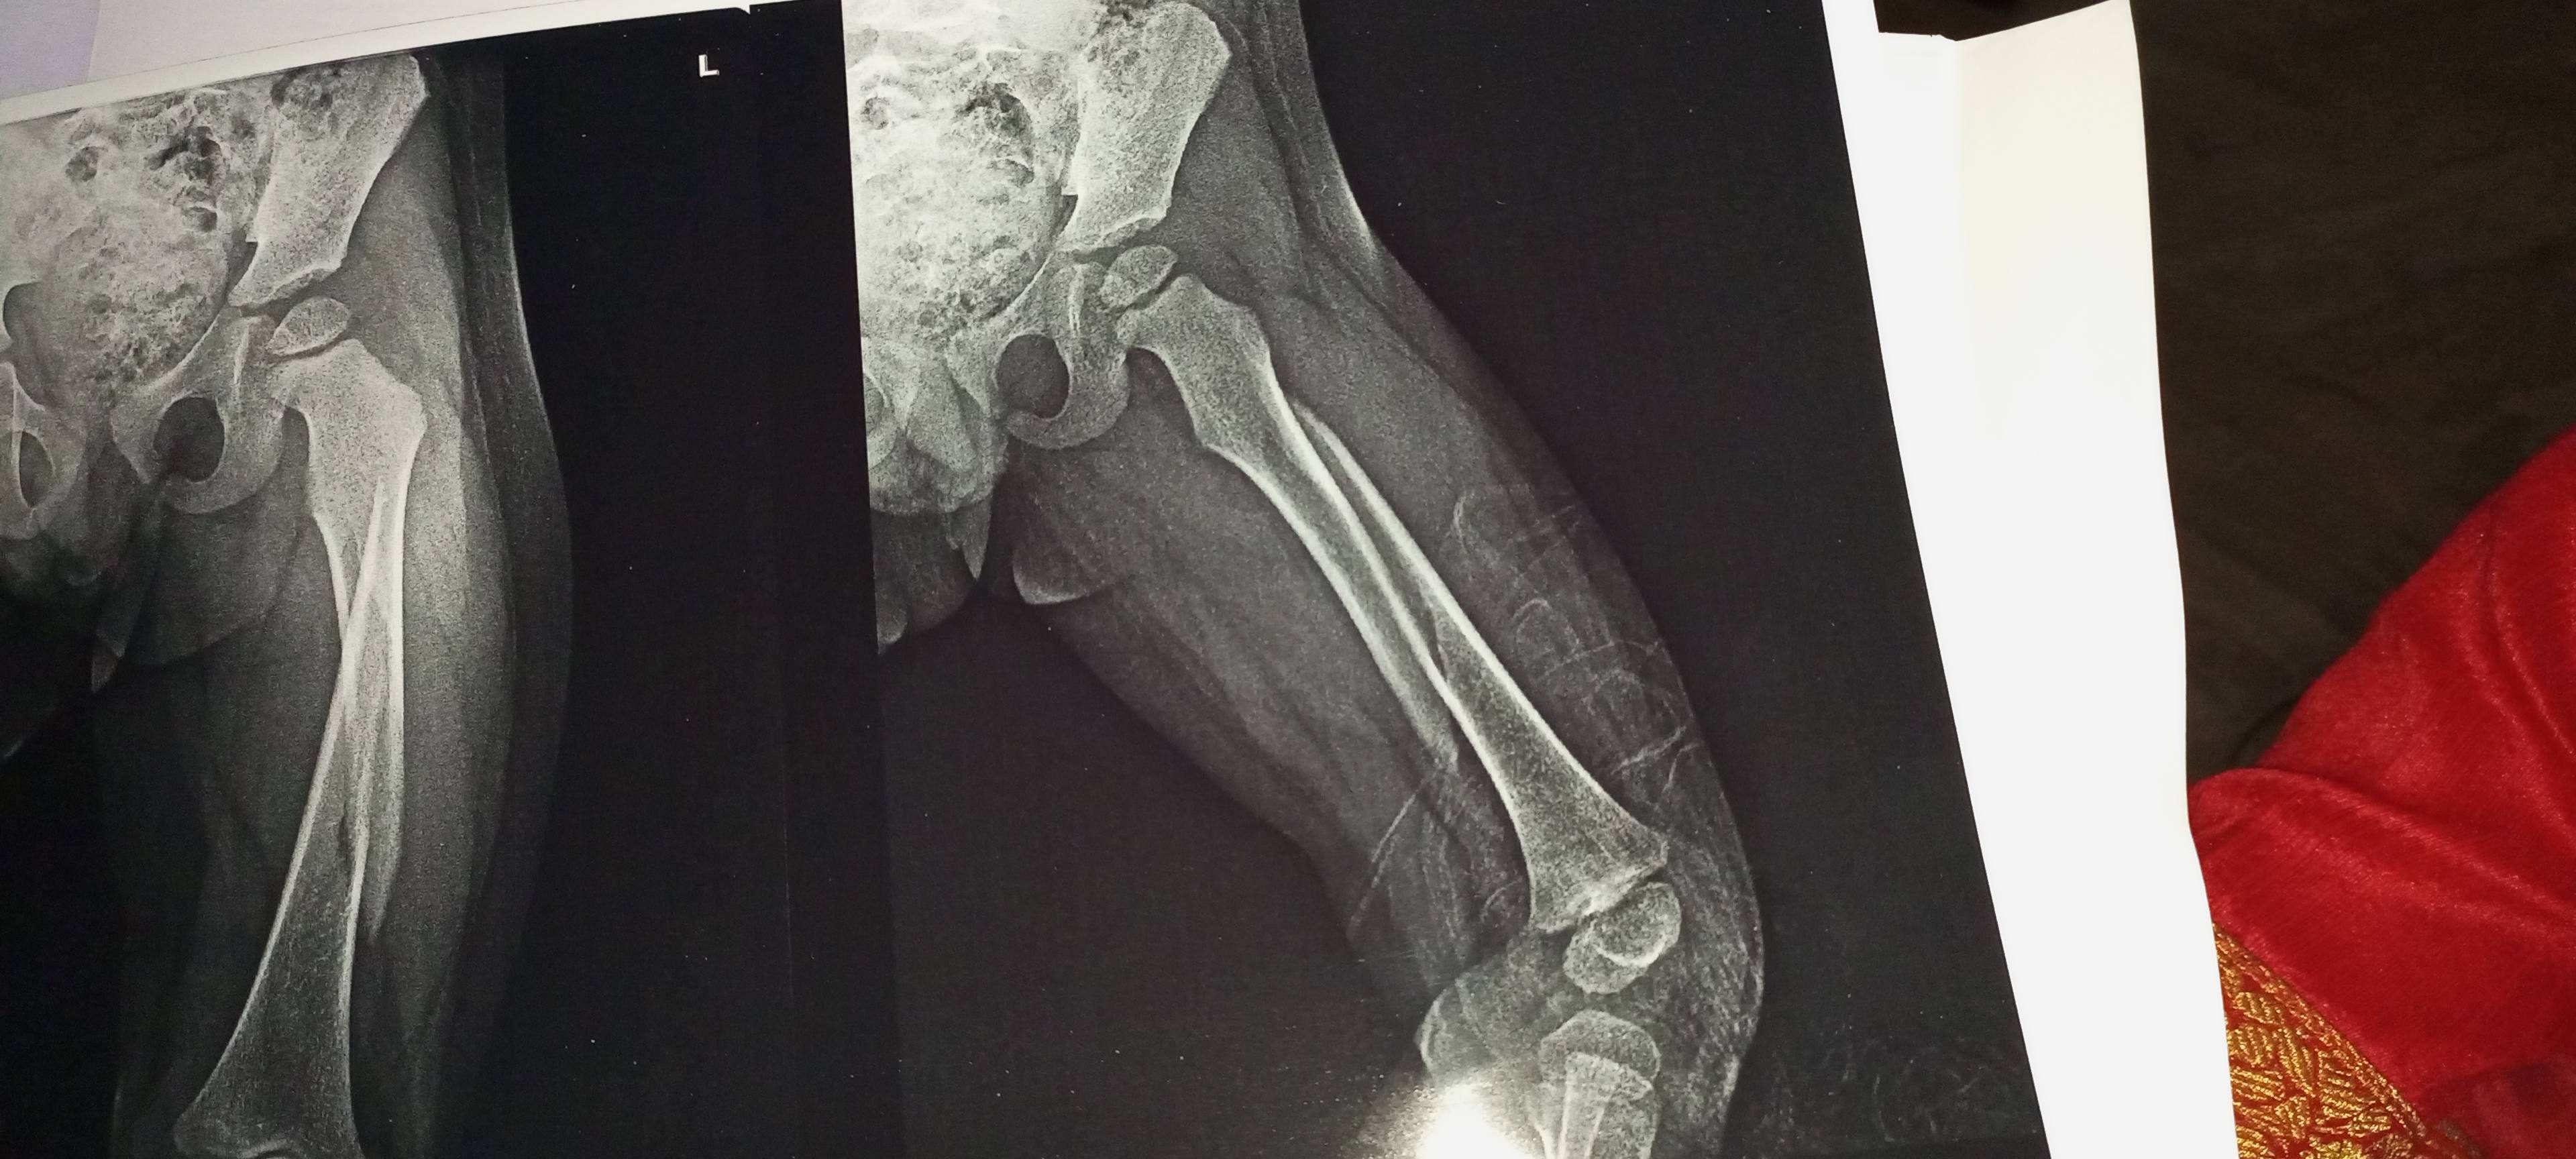

Sir i want to say that my 1st month x ray after surgery is same with the fresh x ray of 2.25 month after surgery.what should i have to do